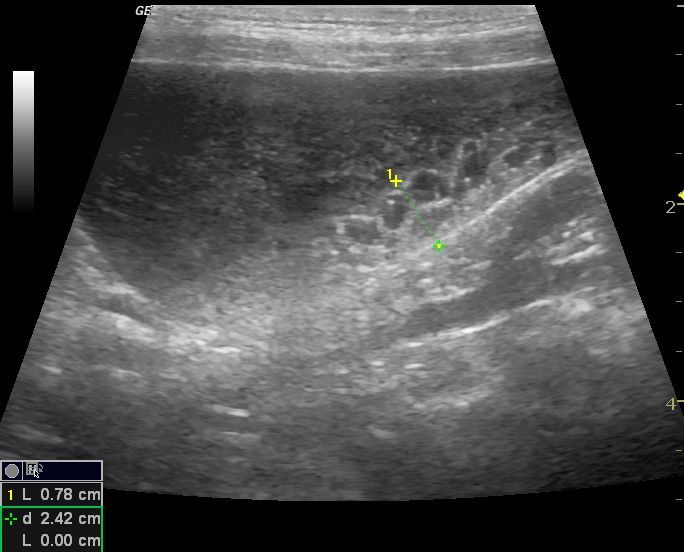

La Ecografía permite una exploración completa de los distintos órganos aportando datos objetivos para conseguir un diagnóstico preciso , establecer un tratamiento adecuado y realizar un seguimiento de cada caso.

La ecografía como diagnótico de gestación es a día de hoy el método más fiable durante el primer trimestre, además nos aporta datos para predecir la fecha de parto, y realizar un seguimiento del desarrollo de los fetos, pudiendo evaluar el estres fetal.